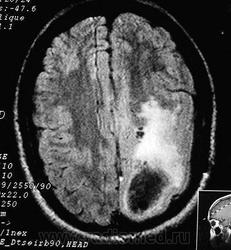

ГМ. Полимикрогирия. +

Полимикрогирия.